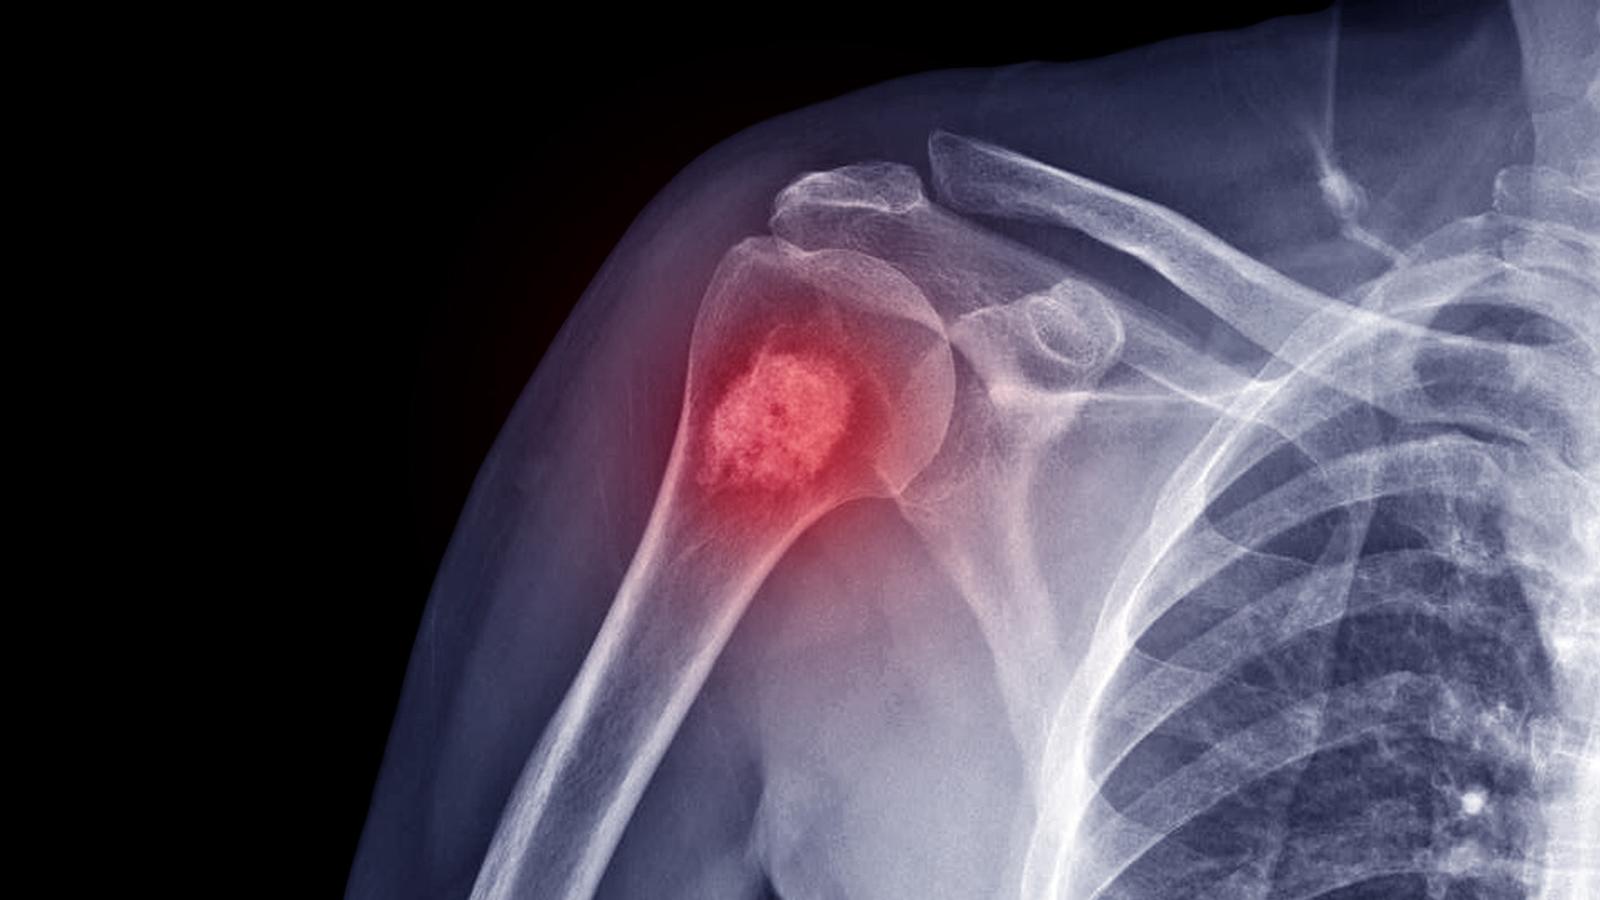

Als Knochentumor wird eine gutartige (benigne) oder bösartige (maligne) Geschwulst des Knochens bezeichnet.

Als Knochentumor wird eine gutartige (benigne) oder bösartige (maligne) Geschwulst des Knochens bezeichnet (Tumorerkrankungen des Skelettsystems). Dabei unterscheidet man zwischen primären Tumoren, sie gehen vom Knochen aus und sekundären Tumoren, also Absiedelungen von Tumorzellen im Knochen.